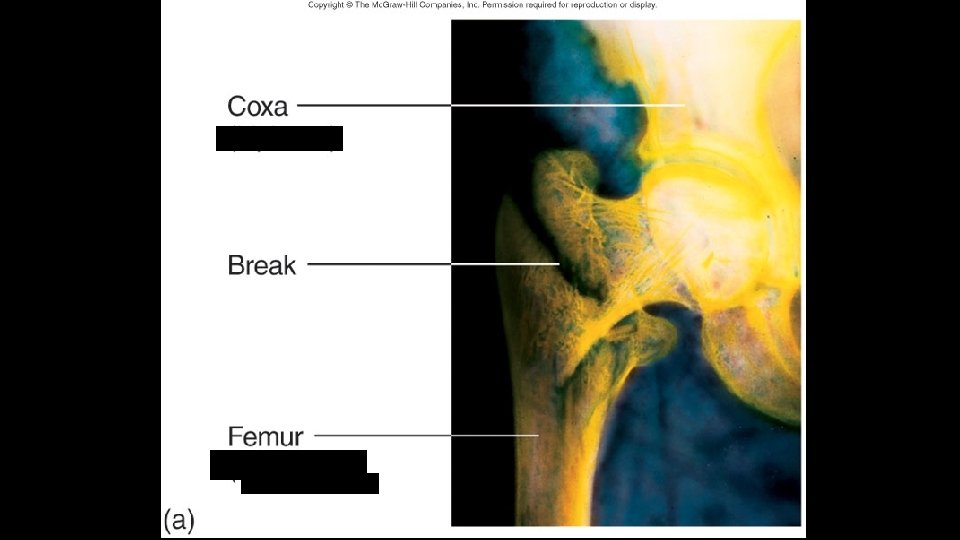

Femur (Largest Bone in the Body)

Bone Fractures · A break in a bone · Types of bone fractures · Closed (simple) fracture –does not penetrate the skin · Open (compound) fracture – broken bone penetrates through the skin · Bone fractures are treated by reduction and immobilization Copyright © 2003 Pearson Education, Inc. publishing as Benjamin Cummings Slide 5. 16